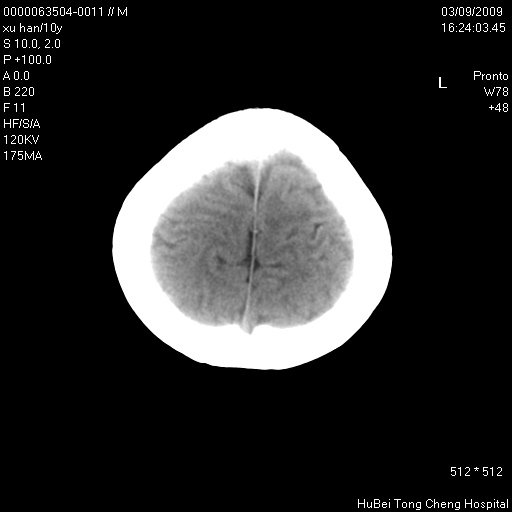

以下是引用道哥在2009-3-9 18:40:00的发言:[br]未见明显异常,必要时mr(dwi)成像。

以下是引用余辉在2009-3-10 11:01:00的发言:[br]考虑双侧海马急性缺氧性损伤